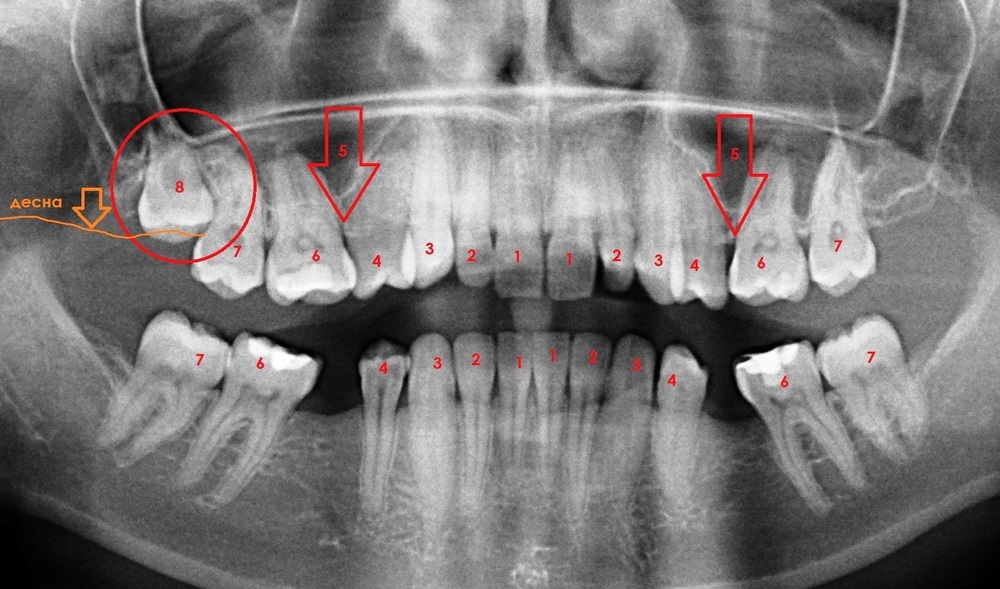

Основные системы и принципы нумерации зубов в стоматологии, удобные схемы с номерами зубов . Система Виола, Хадерупа, Зигмонди-Палмера, почему зубов по номерам больше 32 .

Нумерация зубов в стоматологии . Системы нумерации зубов предназначены для оптимизации процесса диагностирования полости рта . Они позволяют точно заносить добытые сведения в . . .

«Вам нужно срочно удалять 48-й зуб!» - такое заявление стоматолога может всерьез озадачить пациента, ведь еще из школьного курса биологии каждый знает . . .

Как нумеруются зубы в стоматологии? Современные схемы нумерации зубов у взрослых и детей . Расчет стоимости лечения онлайн по снимку!

В статье представлены все утвержденные схемы нумераций и названий зубов в стоматологии для детей Нумерация зубов в стоматологии: полное описание постоянных и молочных зубов .